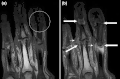

T1-weighted semi-coronal MRI of sacroiliac joints (a) before and (b) after contrast showing active sacroiliitis (arrow). -

Coronal T1-weighted MRI of fingers in PsA. (a) Pre- and (b) post-contrast showing active synovitis at proximal and distal interphalangeal joints (large arrows), joint space narrowing, bone proliferation at proximal interphalangeal joint, erosions at distal interphalangeal joint (white circle), enthesitis medial to proximal interphalangeal joints. -